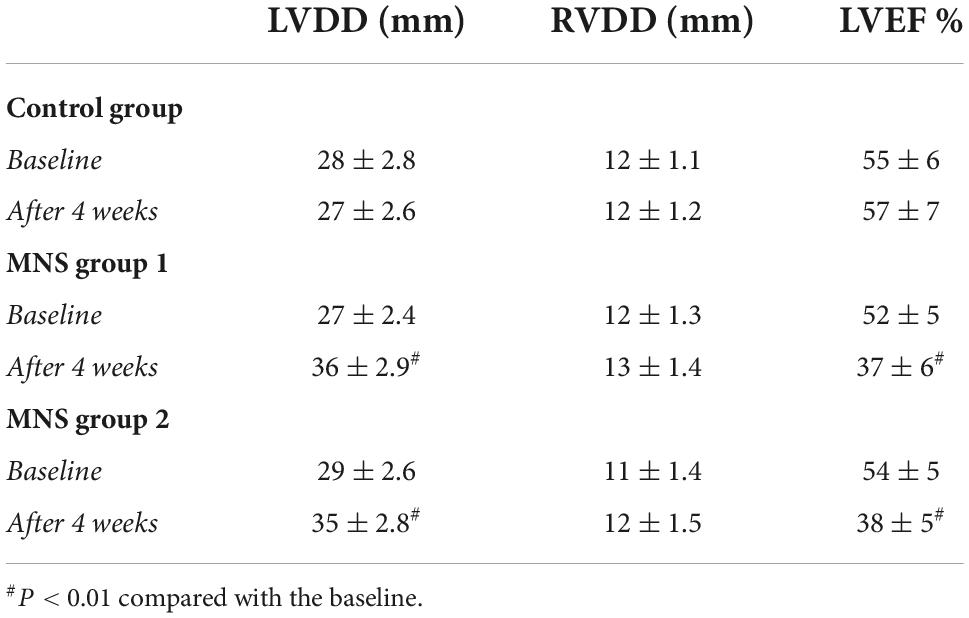

Compared with baseline, in the MNS group 1 and MNS group 2 dogs, there was a remarkable reduction in the percentage of thickening in the left ventricular anterior walls after 4 weeks; in addition, significantly increased LVDD (the MNS group 1 dogs: 27 ± 2.4 vs. 36 ± 2.9 mm, P < 0.01 and the MNS group 2 dogs: 29 ± 2.6 vs. 35 + 2.8 mm, P < 0.01) and reduced LVEF (the MNS group 1 dogs: 52 ± 5 vs. 37 ± 6%, P < 0.01 and the MNS group 2 dogs: 54 ± 5 vs. 38 ± 5%, P < 0.01) were noted. However, there was no significant change in the RVDD between baseline and after 4 weeks in the MNS group 1 and the MNS group 2 dogs. Moreover, we reported no significant differences in the LVDD and RVDD between baseline and after 4 weeks in the control group (Table 2).

Table 2. Changes in echocardiographic data at baseline and after myocardial infarction (MI) 4 weeks.